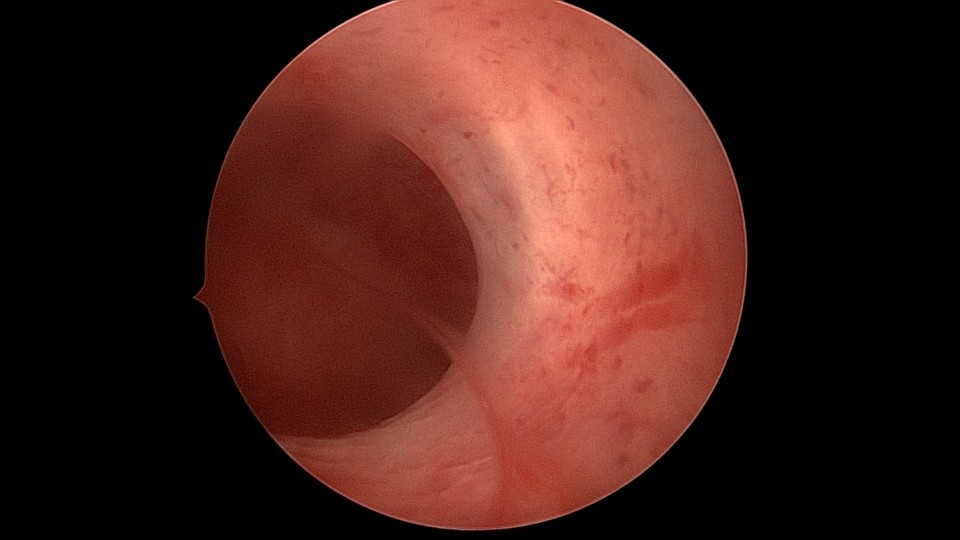

患者29岁,G1P0,继发不孕,2020年8月宫腹腔镜探查,大网膜与腹前壁多处粘连,子宫后壁与直肠前壁广泛粘连,宫腔中央型宽大柱状粘连,宫腔两侧少许粘连。电钩分离盆腔粘连,冷刀分离宫腔粘连,恢复宫腔形态,显露双侧输卵管开口,术中美兰通夜,双侧输卵管通畅。2020年10月宫腔镜二探取球囊,宫腔形态正常,双侧输卵管开口可见。2021年3月自然妊娠,外院足月分娩。现34岁,G2P1。